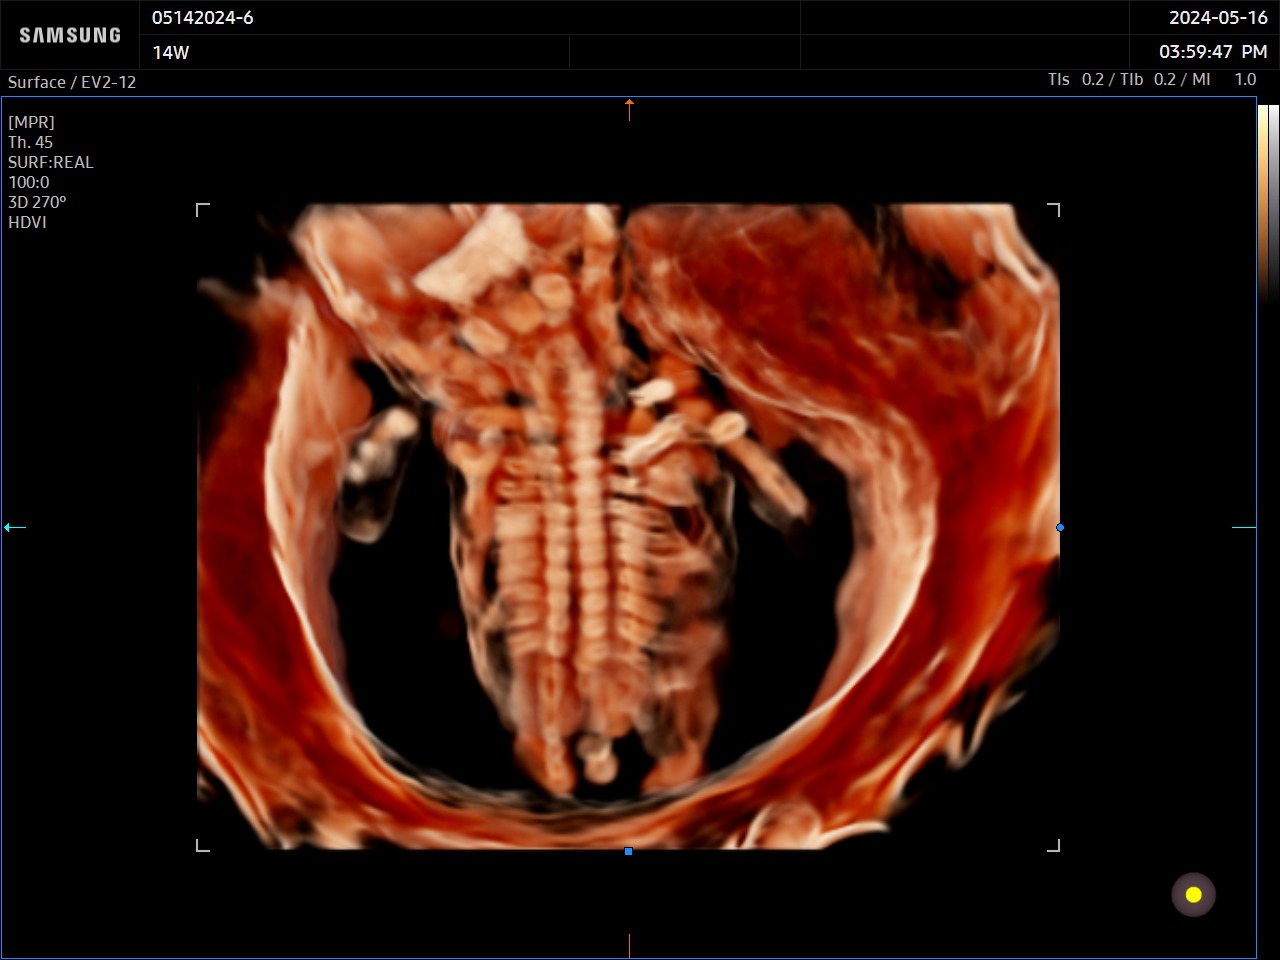

CrystalVue™ est une technologie avancée qui permet de visualiser sur un rendu volumique, les structures tissulaires et les structures osseuses. Ce mode utilise la superposition des différentes échogénicités afin de permettre la visualisation de toutes les structures sur un même volume.